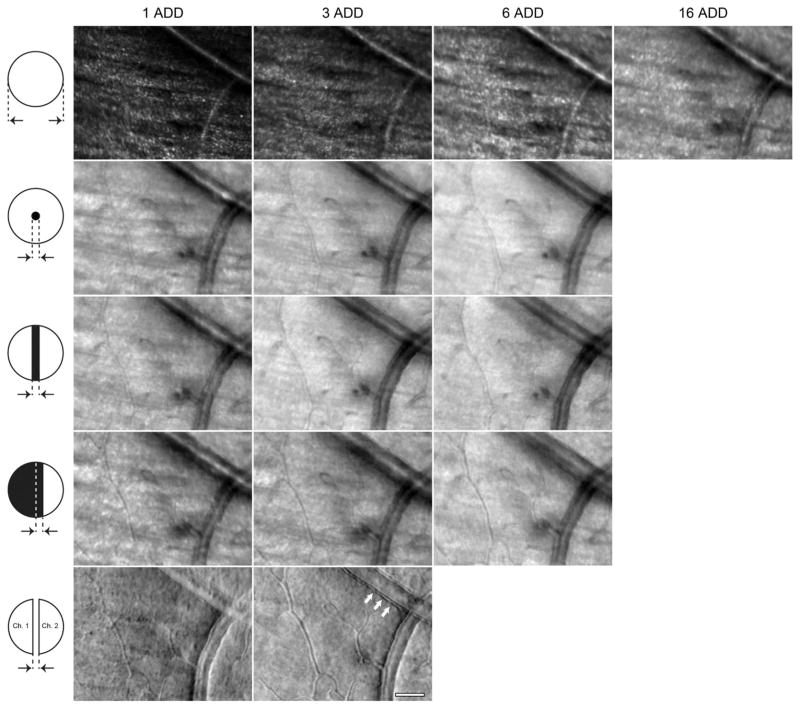

A previously described AOSLO [30] was modified to compare five different detection schemes. This was achieved by placing different spatial filters in the retinal conjugate plane in front of the light detector(s). The spatial filters used, shown in Fig. 1, were:

Masks placed in the retinal conjugate plane in front of the AOSLO point detector(s), with black denoting opaque regions. The arrows indicate the sizes referenced in the text. Split-detection is the only detection scheme with two detectors (Ch. 1 and 2).

Fig. 5.

Reflectance AOSLO images at 5° nasal and inferior from fixation collected in subject JC_0200 using the following detection apertures: circular, annulus, circular with an opaque filament, knife-edge, and split-detector. Scale bar is 50 μm across.

Fig. 6.

Perfusion maps corresponding to the image sequences averaged to create Fig. 5. Scale bar is 50 μm.

In retinal locations with relatively thick NFL, such as that shown in Fig. 5, the strong reflectance signal from the NFL prevented the visualization of the microvasculature for all circular detector sizes. Also, the granular NFL appearance means that residual errors in image registration create larger granular artifacts in the perfusion maps that cover the entire image.

When imaging with the annular apertures or circular apertures with filaments, only the inner diameters were varied while the outer diameter was maintained at 16 ADD. The reflectance images (second and third rows of Fig. 2) and vascular cross sections (same rows, Fig. 4) did not change noticeably with either type of detection aperture or inner obscuration size. As with the large circular apertures, the capillary profiles were typically (but not always) bipolar. The perfusion maps on the other hand (Fig. 3 and red dashed curves in Fig. 4), showed a clear reduction in contrast with increasing obscuration size.

The same observations can be made from the images at 5° inferior and nasal from fixation (second and third rows of Figs. 5 and 6). Notably, the larger obscurations resulted in a stronger attenuation of the NFL signal, thus revealing the capillary network that serves the NFL more clearly. The perfusion maps at this retinal eccentricity (Fig. 6) were comparable to that of the FAZ, showing a contrast reduction with increasing inner diameter. This suggests that the confocal signal, which is blocked with the central circular (annular aperture) or rectangular block (filament), contains a nonnegligible amount of flow information.

3. Knife-Edge

Similar to the annular and circular apertures with a filament, the reflectance images in Fig. 2 showed comparable capillary walls contrast regardless of the position of the straight edge of the obscuration. There was, however, a contrast reduction in the perfusion maps with increasing aperture blockage, albeit smaller than that observed when using filaments or circular apertures.

At the more eccentric retinal location (Fig. 5), the blocking of the confocal signal attenuated the light from the NFL, revealing the microvasculature in both the reflectance and perfusion maps. Of note, is that the contrasts and/or sharpness of the cellular structures in the largest blood vessel walls increased with obscuration size. In this imaging modality, there was also a clear bipolar appearance of the vessel walls regardless of the vessel orientation.

4. Split-Detector

One of the most notable features of the split-detector images is that low spatial frequency background variations attenuate with increasing detector separation. These images show high bipolar capillary contrast and what appears to be a mosaic of cellular structures, although without well-defined edges that would permit cell counting. The corresponding perfusion maps show moderate contrast with very uniform and minimal background, which makes these images the most amenable to automated vasculature segmentation when compared to the other detection schemes discussed previously.

When imaging at the more eccentric retinal location (Fig. 5), the NFL signal in the split-detector images was virtually negligible. This was likely the result of blocking the confocal signal as well as taking the difference between the two halves of the image plane signals. As with the images from the edge of the FAZ, the perfusion maps derived from the split-detector image sequences had the least image registration artifacts because of the substantial reduction of the NFL signal. Furthermore, this technique also provides the strongest (bipolar) contrast of the cellular structures flowing within the blood vessels (Media 1 in Fig. 10) and forming the walls of the larger vessels (Fig. 5).

An additional benefit of split-detection is the contrast in the wall structures in the large vessels (white arrows in bottom right panel of Fig. 5). These structures correspond well with those reported by Chui et al. [27], and they are likely endothelial cells and/or pericytes.